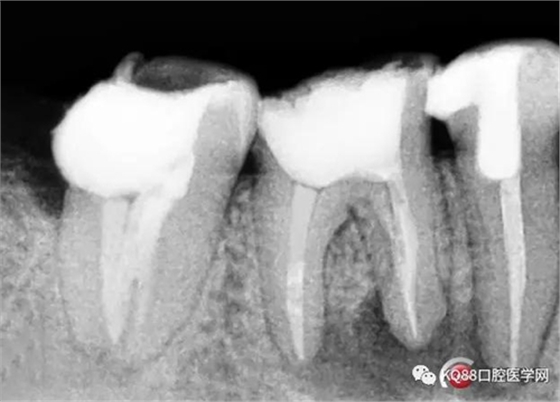

兩牙確定工作長度